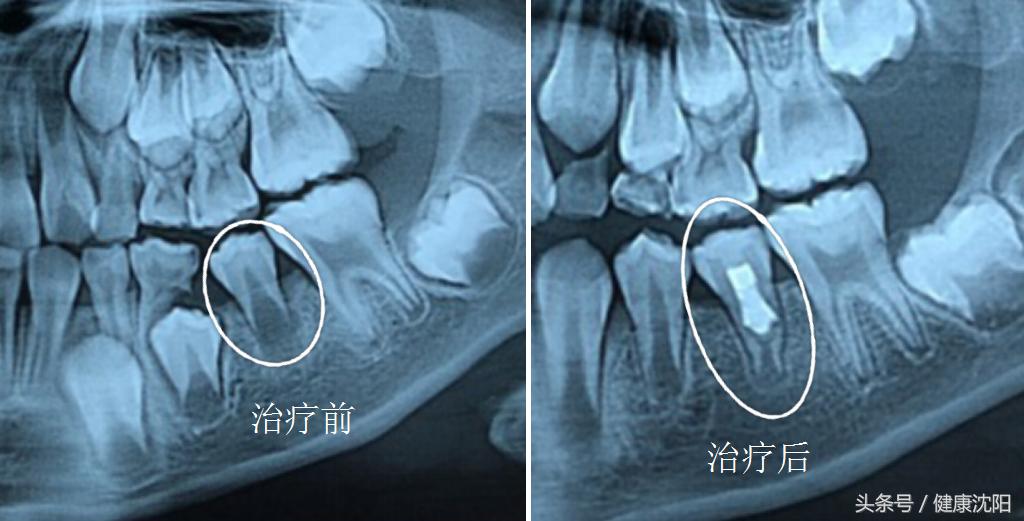

对于未发育完全即根尖孔未闭合的年轻恒牙,因外伤、龋坏或畸形中央尖破坏等导致的牙髓炎症或根尖病变,传统的治疗方法无非首选根尖诱导成形术或mta根尖封闭术。

牙髓再生是基于生物支架提出的,用于取代受损的牙本质、牙根结构及牙髓-牙本质复合体等结构。这种新的模式已经成为另一种除了治疗根尖周炎外,还可以促进正常牙髓的生理功能,包括牙根继续发育,提高免疫力,从而给牙髓再一次的活力。

诱导根尖组织出血形成血凝块作为蛋白组织支架是目前牙髓血运重建中的主要方法。血凝块不仅可以使细胞表面整合因子与纤维块产生黏附,选择性吸附细胞,还包含丰富的生长因子,促使细胞生长分化。(血小板分泌的生长因子包括血小板衍生生长因子(PDGF)、转化生长因子β1(TGF-β1)、血管内皮生长因子(VEGF)和表皮生长因子(EGF)。)动物实验证明血凝块的形成有利于根管内硬组织沉积及活组织形成,促进根管壁增厚和根尖闭合。